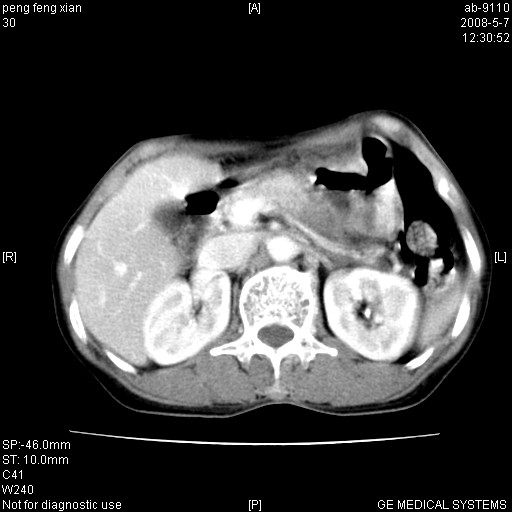

女,56岁。b超左一腹包块,考虑胃肠道肿瘤。

胃体部胃壁增厚,不均匀性强化,与胰腺分解欠情.

考虑:胃癌,胰腺受侵待除外.

鉴别:胃淋巴瘤(强化不明显)

建议:胃镜检查.

典型胃癌胰体尾部受侵。

胃壁增厚,左前胸壁局限性隆起,考虑胃癌可能性大,建议做胃镜